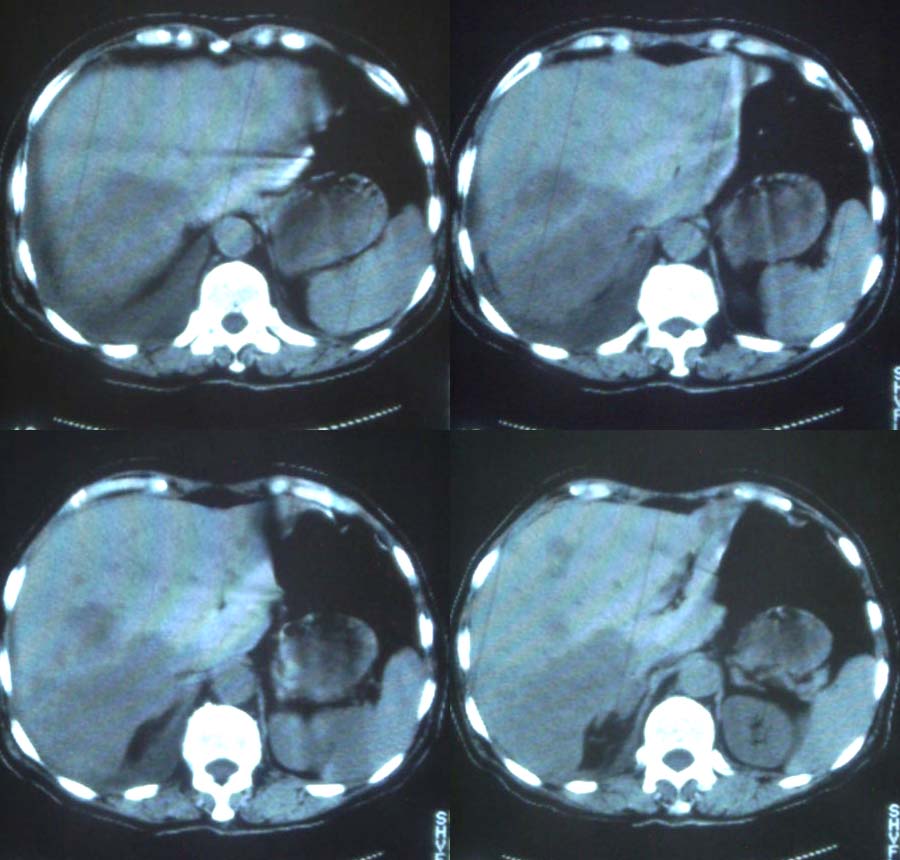

这是一个75岁女性患者,右下腹痛。胸透示,右下肺可见大片状高密度影,右侧胸腔积液。请各位老师帮忙看看腹腔都有什么病变,谢谢!

右侧中心型肺癌伴大量胸腔积液、肝转移、右肾上腺转移。

考虑:1、肝脏、右侧肾上腺转移

2、右侧大量胸腔积液伴下叶肺不张,待除外右肺癌

3、建议进一步检查胸部 明确诊断

再者,肝的转移灶一般显示为多发性大小不等的低密度肿瘤结节,也可为单发结节。多在低密度病变内存在更低密度区域,从而显示为同心圆状或等高线状双重轮廓--即牛眼为其特征。本例肝右叶后段的大块状病灶无论形态、密度均不具备转移灶的特点。

倒是反过来推断合理一些,即:肝右叶后段原发性肝癌肝内转移,直接侵犯右膈肌以及胸膜引起大量胸腔积液更为妥当。同理,右肾上腺以及右下肺的病灶均为直接蔓延侵犯。

1、分析:(1)女性75岁;(2)单侧大量胸腔积液;(3)右侧肺门区团块影,单纯的压迫性肺不张?肿块?;(4)肝脏内多发结节影,大小不等,多结节型肝癌?肝癌并肝脏内转移?(5)肝脏内结节病灶中心有更低密度区;(6)右侧肾上腺不规则软组织灶;(7)肝脏各叶比例正常,脾脏不大。

2、诊断:肺癌肝脏、肾上腺转移并右侧胸腔积液。应该没问题吧?